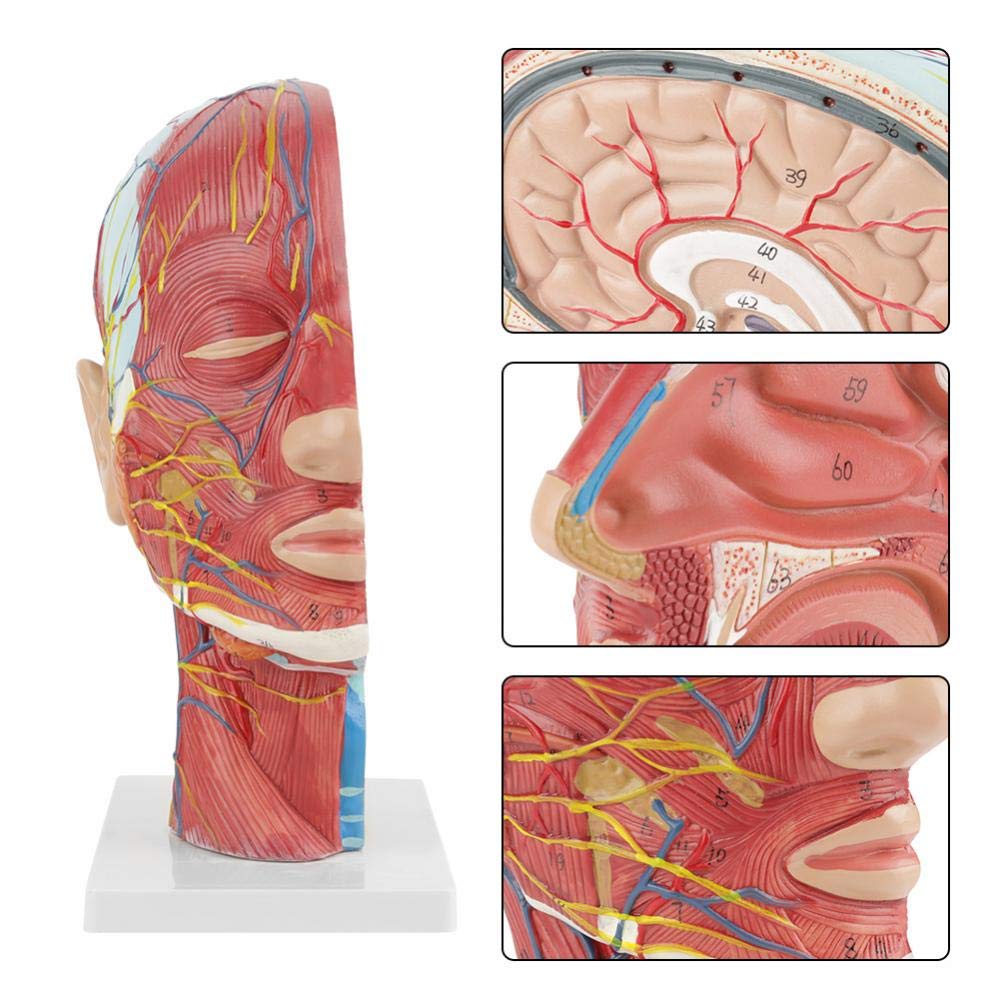

Modelo de anatomia de meia cabeça e pescoço humano modelo neurovascular superficial

Modelo de anatomia de meia cabeça e pescoço humano modelo neurovascular superficial

| Nome do produto | Crânio humano com modelo neurovascular muscular |

| Características | O modelo mostra a morfologia local dos lados interno e externo da seção sagital mediana da cabeça e pescoço, bem como as estruturas dos vasos sanguíneos e nervos, e há 84 partes indicando sinais no total. |

【1: 1 LifeSize】 Seção mediana de 1: 1 Modelo muscular vascular neural superficial grande de cabeça e pescoço natural (lado direito). Bem -estar. Oferecendo uma gama completa de recursos anatômicos.

【Modelo superficial do músculo neurovascular】 Números altamente detalhados, marcados e destacáveis, aprofundar o entendimento dos músculos superficiais, vasos, nervos e as estruturas internas da cabeça e pescoço. Artéria vermelha, azul-veia, nervo amarelo.

【Apresenta】 mostra os músculos superficiais da face exposta; os vasos sanguíneos superficiais e os nervos do rosto e do couro cabeludo; as estruturas internas da glândula parótida e do trato respiratório superior; A estrutura de seção transversal sagital da coluna cervical.

Este modelo mostra detalhes do pescoço da cabeça direita e da seção sagital média do humano. incluindo o superficial

músculos da face exposta; os vasos sanguíneos superficiais e os nervos do rosto e do couro cabeludo; as estruturas internas

da glândula parótida e trato respiratório superior; A estrutura de seção transversal sagital da coluna cervical.

O modelo mostrou a morfologia local das seções sagitais mediais e laterais da cabeça e pescoço e suas estruturas vasculares e nervosas, com um total de 100 indicadores do local.

Este modelo é um modelo muscular neurovascular superficial grande e pescoço natural, um componente 1, mostrando os detalhes da cabeça e pescoço direito humano e seção sagital mediana, incluindo os músculos superficiais expostos da face, vasos superficiais do rosto e do couro cabeludo, nervos e a estrutura medial da glândula parótida e do trato respiratório superior, e a estrutura da seção sagital da coluna cervical